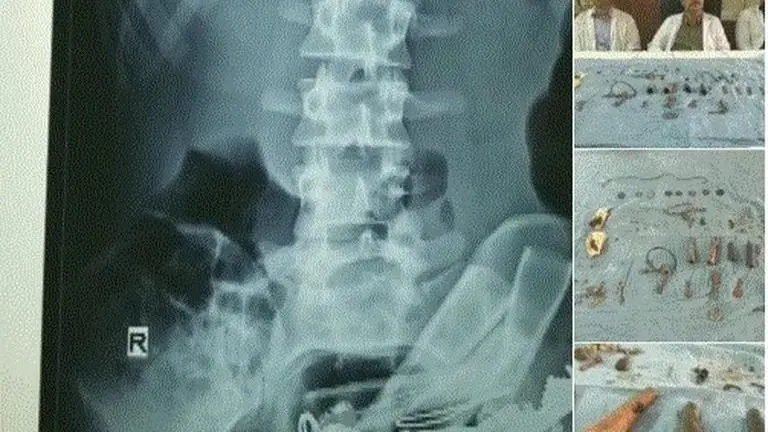

In an atypical case, doctors of a government hospital here have removed around 80 objects including "chillam", keys and coins from a mentally-ill patient's stomach in Udaipur on Monday. A team of four doctors conducted the operation which took 90 minutes.

"This could be considered a strange case. The man was admitted in the hospital complaining about a severe stomach ache. He was asked to undergo X-Ray. We were stunned to see small and big metal objects including nails inside his stomach," Dr DK Sharma told ANI.

Without any delay, doctors readied the patient for operation and removed the objects weighing in total 800 gm. Doctors discovered that the patient is mentally ill and an addict.